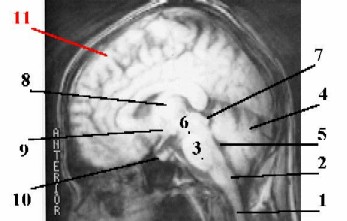

1. Продолговатый мозг (2) - это непосредственное продолжение спинного мозга (1) в ствол головного мозга.

2. а)

Собственно задний мозг включает две части:

варолиев мост (3) (расположенный вентрально, у основания мозга) и

мозжечок (4) (расположенный дорсально).

Магнитная резонансная томография (МРТ) головы.

б) Остатком полости заднего мозгового пузыря является IV желудочек (5) мозга, находящийся на уровне продолговатого мозга и мозжечка.

3. а) Средний мозг тоже имеет две части; его составляют

ножки мозга (6) - проводящие пути к переднему мозгу и

лежащая над ними пластинка четверохолмия (7).

б) Остаток полости среднего мозгового пузыря - узкий канал, т.н. сильвиев водопровод.

Схема - сагиттальный срез головного мозга человека.

4. В промежуточном мозгу – опять-таки две части.

Зрительные бугры (8) (в единственном числе - thalamus) - большие парные скопления серого вещества, между которыми находится полость III желудочка - остаток полости  переднего мозгового пузыря.

Гипоталамическая область (на уровне нижних отделов III желудочка и под ним) включает высшие центры регуляции эндокринной системы -

собственно гипоталамус (9) и

гипофиз (10).

5. а) Конечный мозг содержит

большие полушария (11) и

подкорковые ядра.

б) В полушариях находятся боковые желудочки, которые, как и III желудочек, происходят из полости переднего мозгового пузыря.